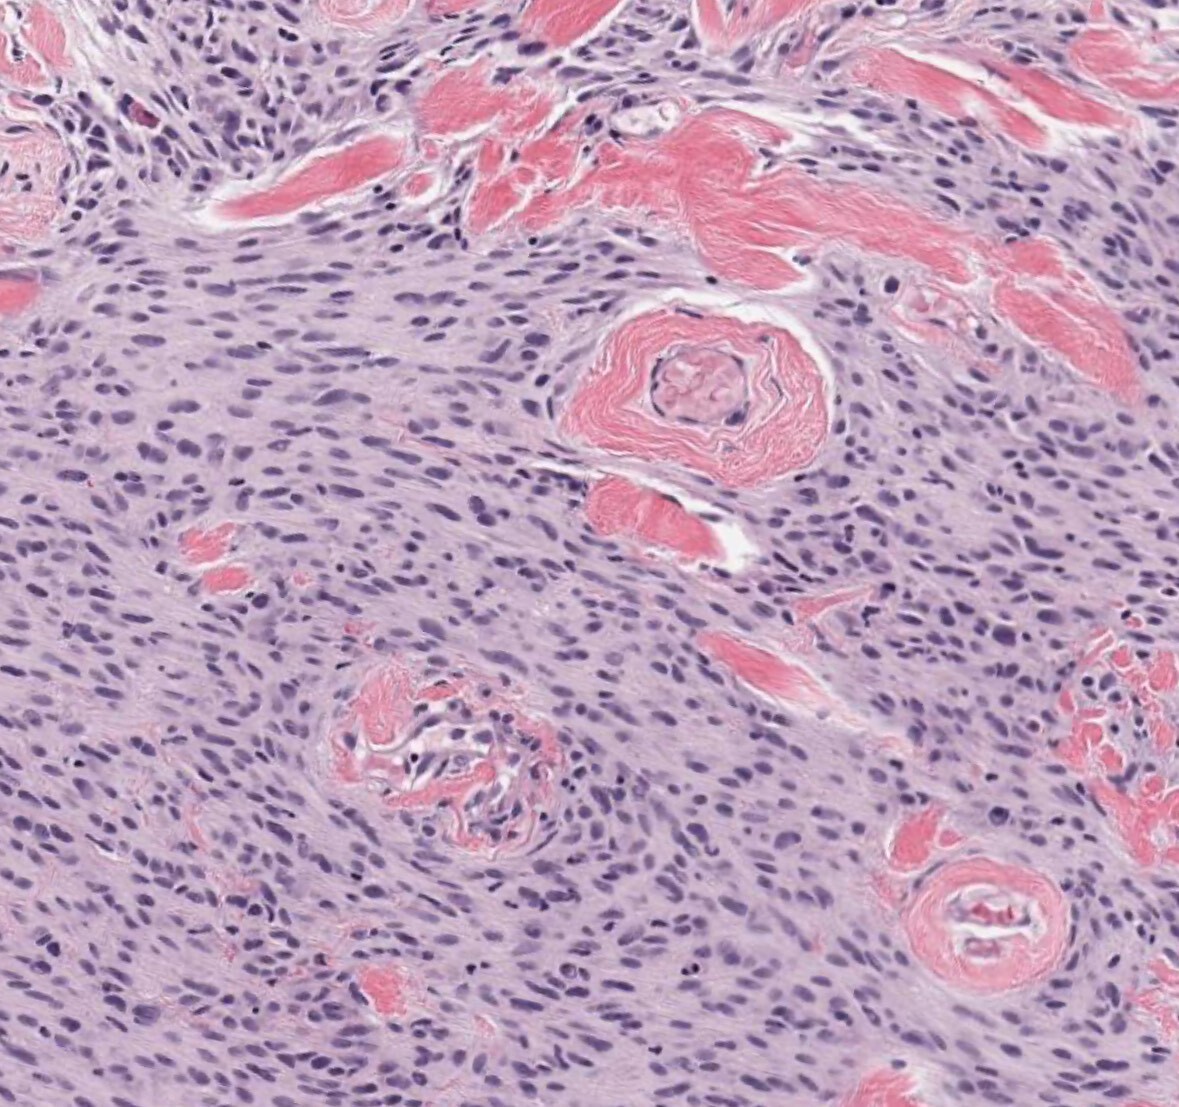

Myofibroblastoma

Bland, spindled cells composed of fibroblasts and myofibroblasts that are arranged in short, haphazardly intersecting fascicles.

Interspersed thick collagen bundles are often present. Minimal mitoses and atypia.

Presents as a slow-growing, painless mass that is well-circumscribed and unencapsulated.

IHC: Loss of RB1, spindle cells are positive for desmin, BCL-2, CD34, ER, PR, and AR.

Molecular: RB1 loss, 13q14 deletions (detect by FISH)

Cured by simple local excision.